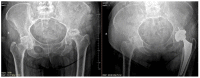

Avascular necrosis (AVN) of the femoral head is caused by disruption of the blood supply to the proximal femur. The alterations in the blood supply may occur following a traumatic event or result from a non-traumatic cause. Femoral neck fracture and hip dislocation and associated surgical procedures, corticosteroid therapy, and alcohol abuse frequently lead to AVN development. Type of fracture (displaced or undisplaced) and time between injury and surgery are the most critical factors in assessing the risk of developing AVN. Diagnosis of AVN can be established based on patients' complaints, medical history, and radiographic findings. There is no consensus on the treatment of patients with AVN to date. Non-surgical methods are dedicated to patients in the early pre-collapse stages of the disease and consist of pharmacotherapy and physiotherapy. Surgery is recommended for patients with advanced disease.